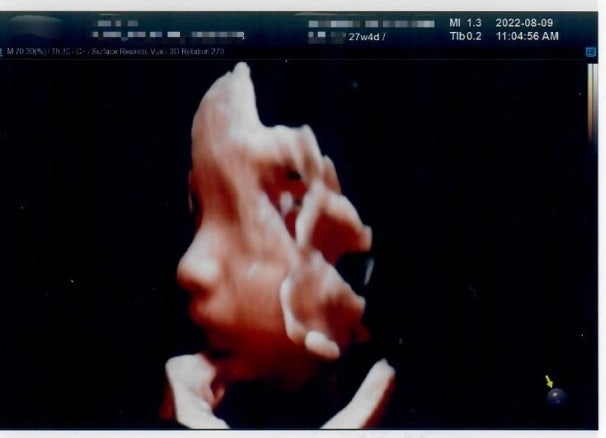

2022 08월 임신 27주차 입체초음파 (일산차병원)

뜬금포로 ㅋㅋ 써보는 우리오꽁이 입체초음파 사진일기 열심히 쓰고싶었지만 삶에 치여 (라고쓰고 게을러터...